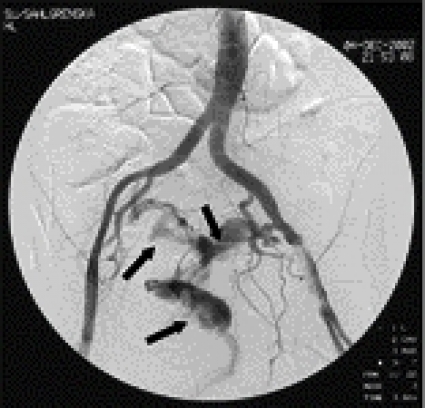

En 5 F införingshylsa infördes i höger femoralartär. Blödningen förmodades härstamma från någon av tarm- eller bäckenkärlen, och initialt gjordes selektiva kateteriseringsförsök. För att påvisa pågående blödning deflaterades aortaballongen från vänster sida. Då profus blödning per rectum åter uppstod utfördes i stället en oselektiv bäckenangiografi, med en kateter placerad distalt i bukaorta. En fistel mellan vänster arteria iliaca externa och rektum påvisades (Figur 2), med en kraftig extravasering av kontrastvätska ut i rektum (Figur 3). En 8 ¥ 30 mm ballongkateter expanderades i arteria iliaca externa över fistelmynningen. Förnyad bäckenangiografi visade upphävd blödning (Figur 4).